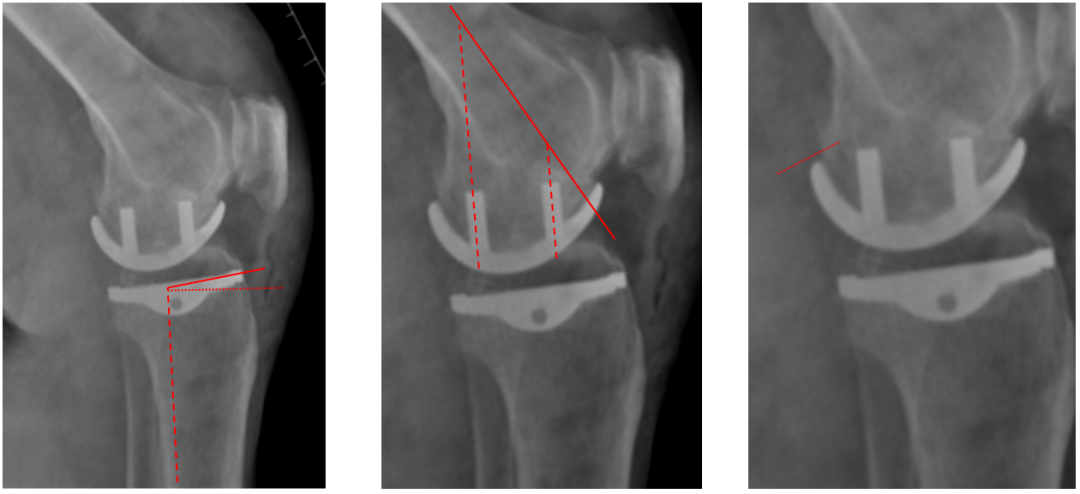

股骨假体偏小

侧位片股骨假体位置:股骨假体偏小,与胫骨假体后缘不齐平;屈曲15°,未包容股骨后髁。

股骨假体偏大

侧位片股骨假体位置:股骨假体与胫骨假体不匹配,股骨假体大一个型号,屈曲45°,后缘空虚。

股骨假体屈曲角度大

侧位片股骨假体位置:股骨假体与胫骨假体匹配,股骨假体屈曲62°,前缘翘起。